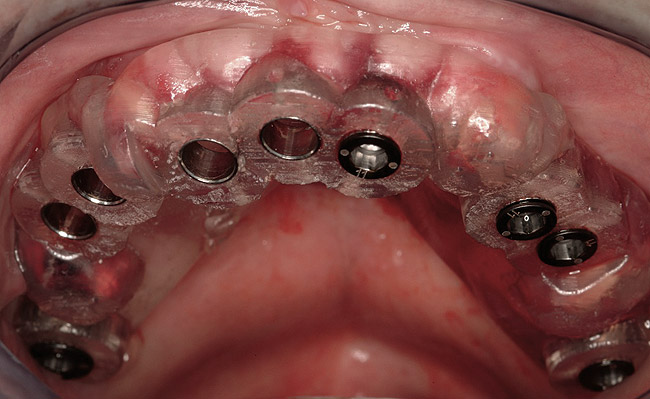

Figure 1  Note wide flap reflection necessary for titanium mesh removal and implant placement. The apical extent of the flap is necessary not only to remove the mesh but also two fixation screws that need to be placed at a safe distance from the apices of the adjacent teeth.

Figure 1